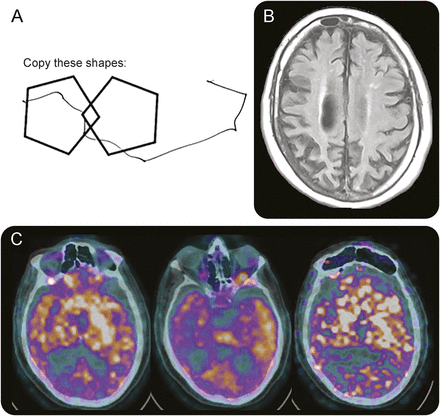

神经系统检查,病人在MMSE得分26/30 (图,一个)。正式的神经测试确认赤字在多个认知域包括记忆、执行功能,注意,相对保存的语言和视觉空间的能力。力量、感觉和反应都是正常的,没有地震或共济失调。他增加了语气、齿轮和减缓手指敲打在左臂,但正常的右臂语气和动作。当试图哑剧使用看到用左手,他的手在圆周运动。当被问及与左手模仿挥手告别,他只是握着他的手平行于表。右撇子的手势是正常的。同样,他间隔的运动症状现在蒙面相,闪烁速度降低,并减少手臂摇摆在左边行走时,虽然没有后退。

(一)病人被要求复制重叠的五角大楼,展示在视觉空间的建设标志着困难。(B)轴向fluid-attenuated反转恢复MRI显示左大于右顶叶和额叶萎缩,年龄比例。(C)正显示左大于右基底神经节的代谢减退,颞叶,顶叶。